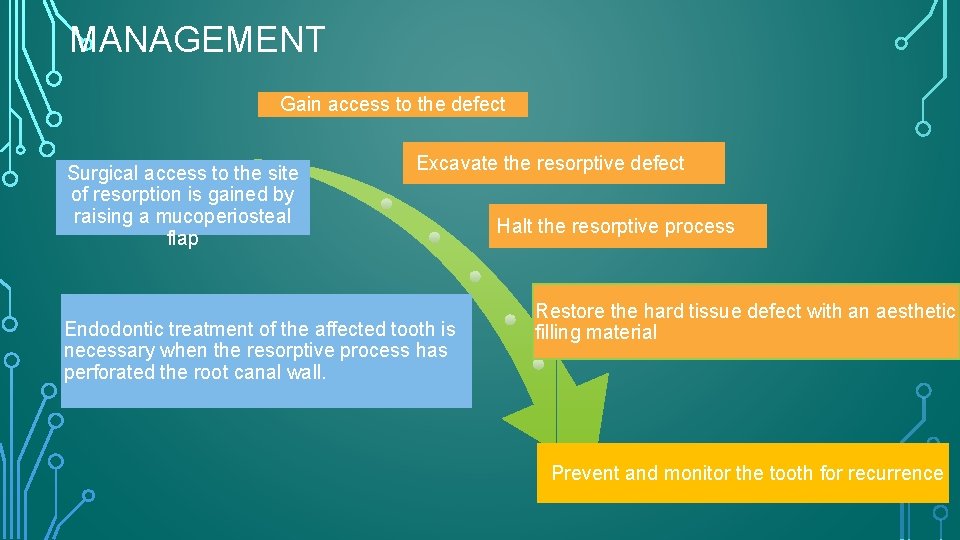

MANAGEMENT Gain access to the defect Surgical access to the site of resorption is gained by raising a mucoperiosteal flap Excavate the resorptive defect Endodontic treatment of the affected tooth is necessary when the resorptive process has perforated the root canal wall. Halt the resorptive process Restore the hard tissue defect with an aesthetic filling material Prevent and monitor the tooth for recurrence